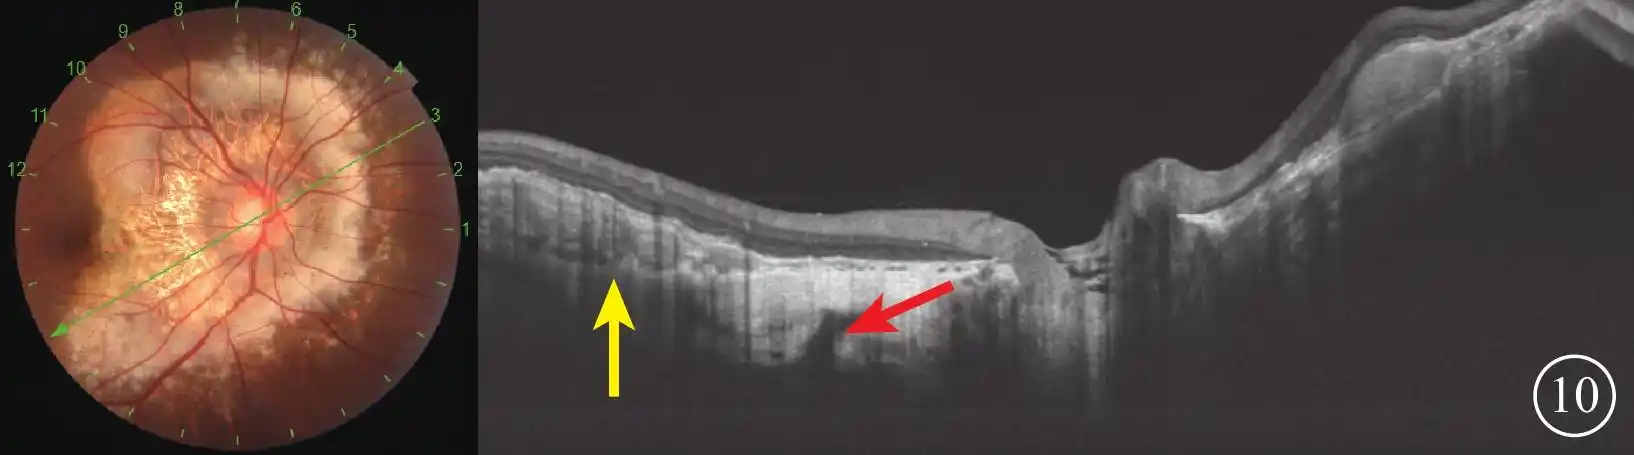

脉络膜骨瘤多种眼底影像特征对比观察

脉络膜骨瘤